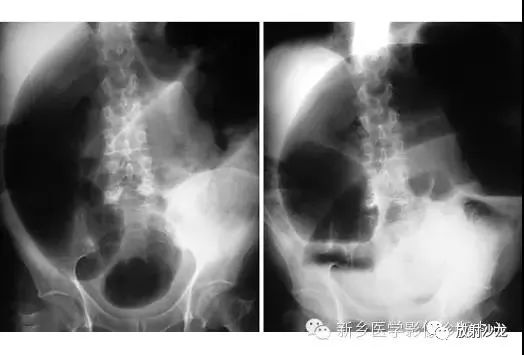

上图符合53岁,女性,肠梗阻所做的腹部平片。发病初所拍图像在左侧,24小时后所拍图像在右侧。是什么原因造成病人梗阻?众多发现都在眼前,不要被箭头影响。

该患者存在一个大的盲肠肠扭转。左侧图像显示一个没有任何可见结肠袋(短箭头),内脏充满大量气体。在升结肠(红色箭头)存在粪便与空气,这表明没有完全阻塞并且一些气体正向远端移动。右图像显示内脏位置的变化,这表明梗阻是非固定的。扭转是由弯曲的箭头所圈出。典型的表现为盲肠头朝向右侧髂窝与肠扭转突出向上朝向左上腹部。